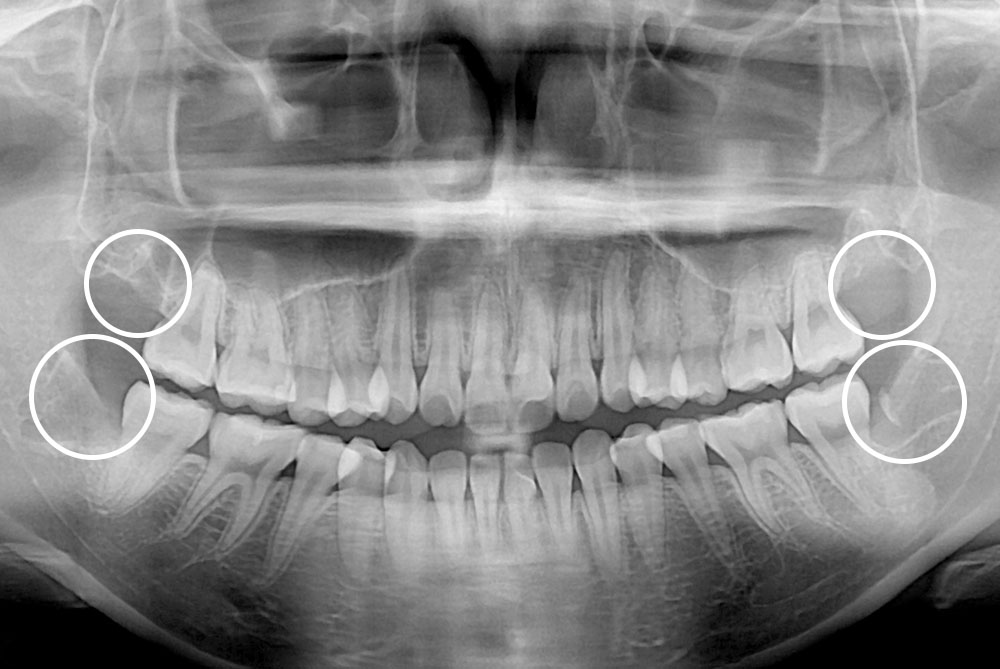

[사랑니] 매복 사랑니 발치

치료전 : 2019-08-26